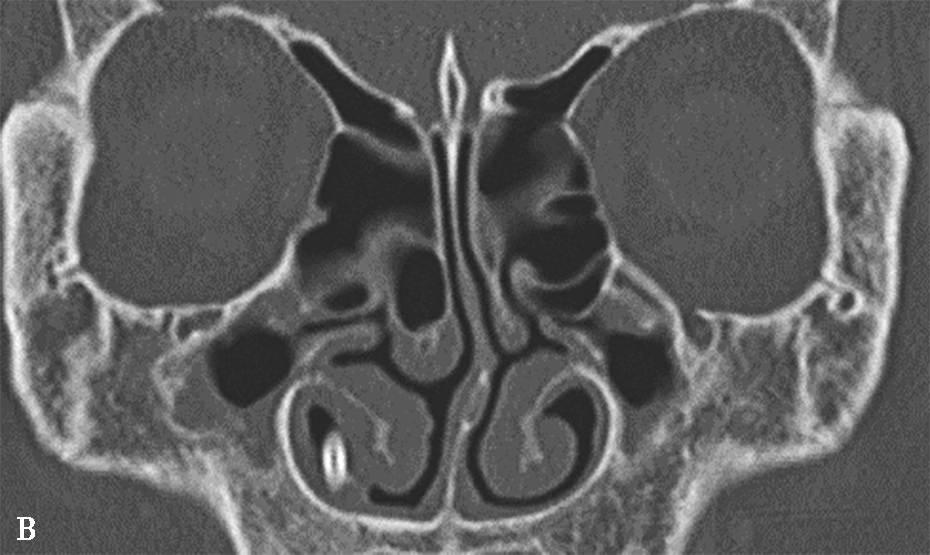

鼻丘气房位于筛漏斗的前上部,与泪骨、上颌骨、筛骨、额骨、鼻骨关系密切。是由筛漏斗直接发展而来。鼻丘气房通常位于额窦底的前部,构成额隐窝的前壁,大小不一,过大、过多可妨碍额窦引流,引起额窦炎。鼻丘气房和钩突眶内壁附着点之间的关系非常密切。当钩突与眶内壁没有附着点时,鼻丘气房不存在;当钩突与眶内壁仅有一个附着点时,鼻丘气房存在;当钩突与眶内壁有两个及以上附着点时,形成上下两个气房,在冠状面观察,偏下的气房称为鼻丘气房,偏上的气房称为额气房,两者内壁均由钩突构成(图1-3-1)。

图1-3-1 鼻丘气房及额气房CT解剖

A~C.鼻丘气房(五角星),额气房(星),钩突(白箭),筛骨纸板(箭头)